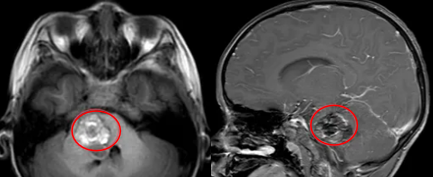

这是一种由异常扩张的血管组成的良性病变通常以散发性、孤立性病灶出现。这些血管像“海绵”一样,结构脆弱,容易渗血,也因此而得名。磁共振成像是诊断海绵状血管瘤的“金标准”,能清晰显示病变的典型“爆米花”样结构。

【点击图片查看案例】5岁的淼淼突现头向左倾斜、呕吐、斜视、行走不稳等症状。医生在淼淼脑干右侧发现了一个大小约29x26x28mm的病灶,诊断为脑干海绵状血管瘤。最终在巴教授主刀下,成功于2024年11月7日实现全切,如今已顺利回归校园。